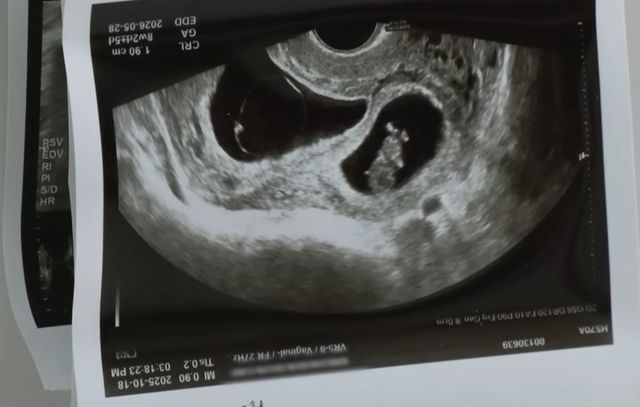

남편을 잃은 쌍둥이 임산부 A씨는 지난 10일 '음주운전에 대한 감형 없는 처벌법 제정에 관한 청원'이라는 제목의 글을 게재했다. A씨의 남편은 지난달 7일 만취 상태의 50대 남성 가해자가 운전한 SUV에 인도로 돌진당해 사망하는 비극을 겪었다. 가해자는 만취 상태로 운전대를 잡고 인도로 돌진하여 A씨 남편을 들이받았고 남편은 심정지 상태로 병원에 옮겨졌으나 끝내 숨졌다. A씨는 청원 글에서 남편과 자신이 한 번의 유산을 겪은 후 간절히 기다리던 쌍둥이 아기를 품에 안을 준비를 하던 참이었다고 비통한 심정을 토로했다.